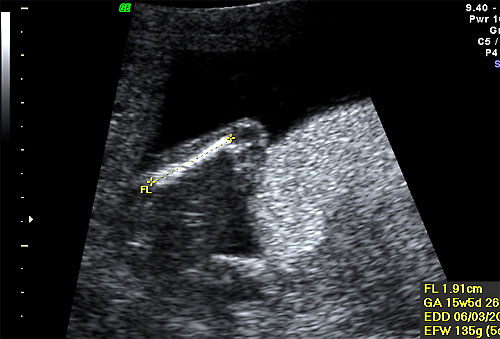

Normal 16 week FL measurement |

Biometry of 16 week fetal ultrasound |